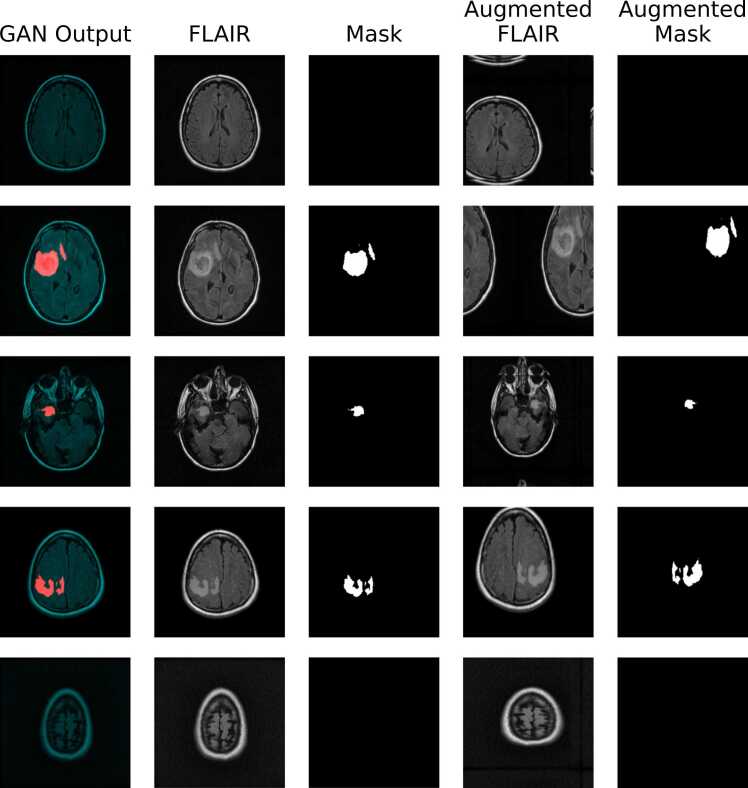

Fig. 3.

Representative sample of synthetic data, decomposed into FLAIR sequence and binary segmentation mask images, before and after applying geometric augmentations. The generated images are essentially indistinguishable from genuine images based on visual inspection, and the GAN achieved an FID score of 14.39. Following geometric augmentations, some of the image compositions are clearly irregular, with brain tissue spread across image boundaries; while this appearance may seem odd to human observers, it is not necessarily deleterious for training CNNs.

After training, the GAN reached an FID score of 14.39. It took approximately two days of continuous training to achieve this FID score; another day of fine-tuning did not improve the FID score. Randomly selected images generated by the trained GAN are shown in Fig. 3. These are effectively indistinguishable from the training set distribution. Importantly, none of the synthetic images were identical to any of those in the training set. Generated FLAIR sequence images and glioma segmentation masks appear to correspond well, with higher intensity pixels indicating tumour tissue that are overlapped by the mask. There is also diversity in the location and morphology of tumour regions among healthy brain tissue. Fourteen batches of 1000 synthetic images were produced, as illustrated in Fig. 2, and split into their corresponding FLAIR images and glioma segmentation masks. These were used cumulatively in fourteen rounds to augment real data and explore the influence of synthetic data augmentation on performance of U-nets trained to perform automatic glioma segmentation.